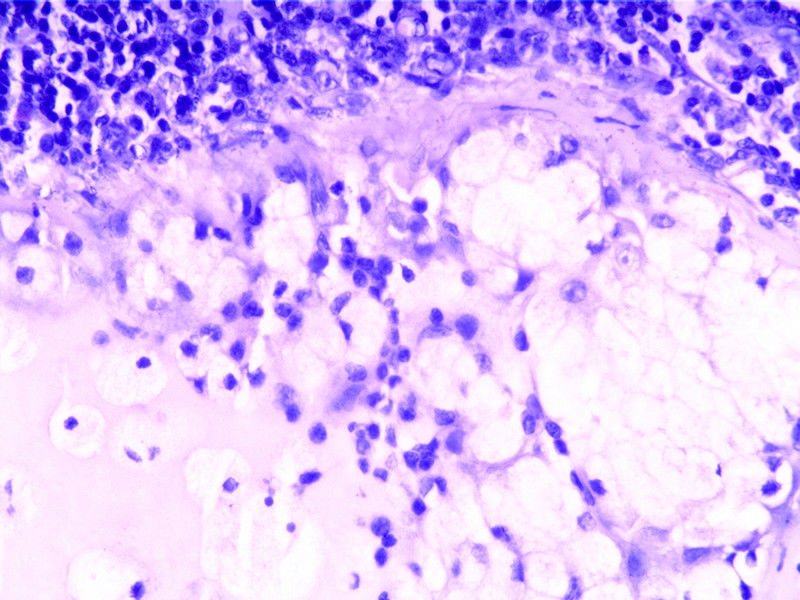

要想Hold住这个肿物的病理诊断,需要了解:

5)上皮与淋巴组织的增殖活性如何?

需要鉴别的肿瘤:

(1)皮脂腺淋巴腺瘤

(2)伴有淋巴组织间质的皮脂腺癌(皮脂腺淋巴腺癌)

(3)良性淋巴上皮病